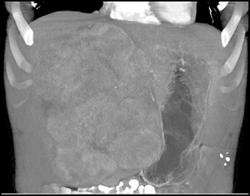

Hepatoma